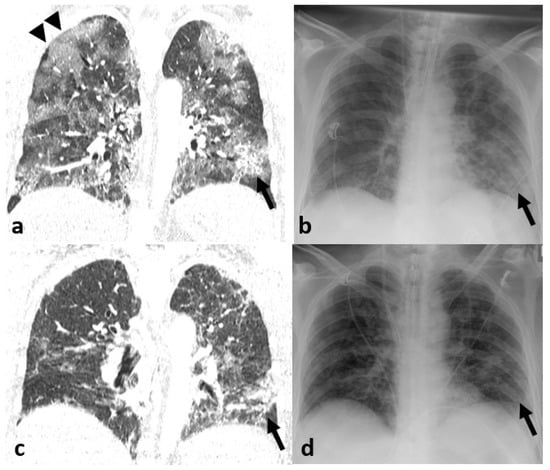

3.3. Imaging Findings